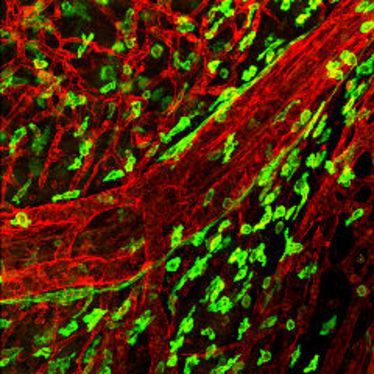

1. Small Animal Imaging Workshop in Münster

1. Small Animal Imaging Workshop in Münster

22.11.2010

- 26.11.2010

1. Small Animal Imaging Workshop in Münster

1. Small Animal Imaging Workshop in Münster

22.11.2010

- 26.11.2010

1. Small Animal Imaging Workshop in Münster

1. Small Animal Imaging Workshop in Münster